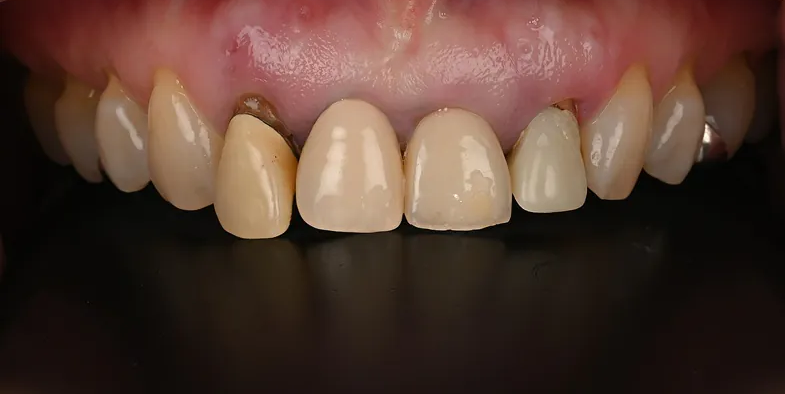

Case3

術前

術中

術後

根面被覆

| 治療名 | 前歯インプラント、根面被覆 |

|---|---|

| 治療説明 | 前歯4本の抜歯が必要となったためインプラントで回復することになりました。右上1,左上1に抜歯と同時にインプラントを埋入しました。右上2、左上2は結合組織移植を行いボリュームを回復することで、見た目と清掃性を向上させました。左右側方歯には根面被覆術を行って歯肉退縮を回復しました。 |

| 治療回数・期間 | 1年 |

| 副作用とリスク | インプラント治療は入れ歯やブリッジと比べて治療期間が長くかかることがあります。インプラント手術と結合組織移植は、違和感、痛み、腫れ、出血などが発生する場合があります。一時的なもので、2日〜1週間で治まります。 |

| 料金(税込) | 骨造成:110,000円(2本:220,000円) インプラント1次手術:220,000円(2本:440,000円) インプラント2次手術:55,000円(2本:110,000円) 結合組織移植:110,000円(4本:440,000円) 上部構造:220,000円(4本:880,000円) 根面被覆:396,000円 合計:2,456,000円 |